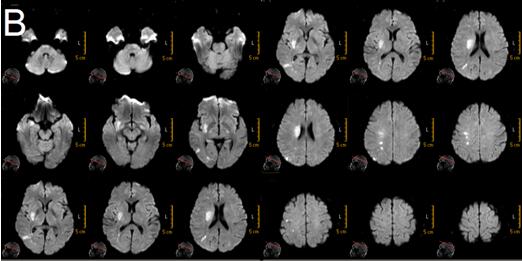

我院为患者立即开通卒中绿色通道,急查头颅DWI:右侧基底节、半卵圆中心、颞叶内侧、顶枕叶皮层多发急性梗塞灶,头部CTA显示右侧大脑中动脉M1段闭塞(图1);头部CT未见急性出血灶。诊断:“1.急性脑梗死;2.右侧大脑中动脉闭塞;3.高血压病2级 极高危组”明确。

图1 B:右侧基底节、半卵圆中心、颞叶内侧、顶枕叶皮层多发急性梗塞灶(2017/9/6 19:17)